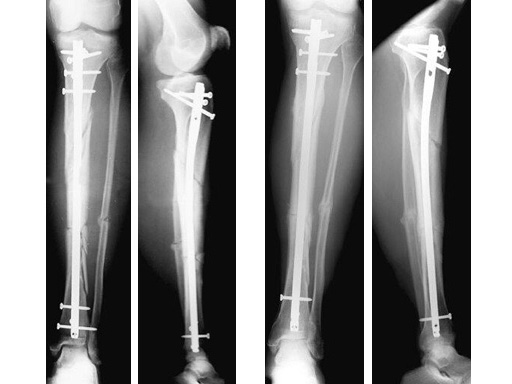

Type III open distal tibial fracture with beginning compartment syndrom following a traffic accident.